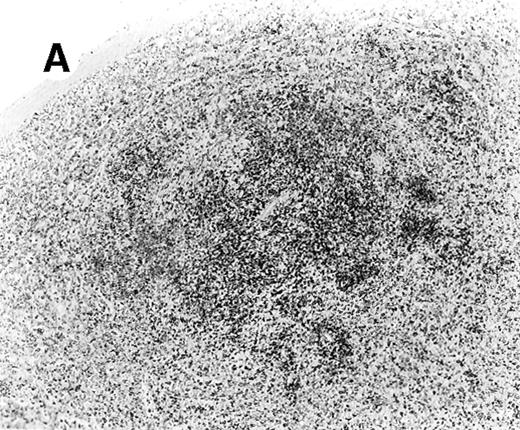

Staining for CD4 and CD8 in spleen from case 4.

(A) Low-power view of spleen shows that the lymphoid nodules are composed predominantly of CD4+ cells. (B) Relatively few CD8+ cells are seen. (C) The CD4+ cells are also EBER1+ (immunoperoxidase stained, hematoxylin counterstained, × 50).

The immunophenotypic features and molecular data are summarized in Table 2. Immunophenotyping was performed on the spleen or liver or both in all cases. The infiltrate in all cases was composed predominantly of CD3+ T cells (Figure3A). CD20 stained attenuated residual B-cell areas in the spleen and only rare scattered B cells were identified within the liver (Figure 3B). Staining for CD4 and CD8 showed that the infiltrate was CD8+ in 2 cases (Figure4A), CD4+ in 2 cases (Figure5A), and in the remaining 2 cases CD4+ and CD8+ cells were noted in approximately equal numbers without clear subset predominance. CD4 highlighted the erythrophagocytic histiocytes (Figure 4B). The lymphocytes in all cases expressed βF1 and TIA-1+ (Figure 4C and D) and were CD56−.

In situ hybridization for EBV using the EBER1 probe showed striking positivity in the majority of the small lymphoid cells in all cases (Figure 4E). Correlation of the EBV positivity with the distribution of CD4/CD8 staining clearly indicated that the EBV-harboring cells were CD8+ in cases 2 and 5 (Figure 4E) and CD4+ in case 4 (Figure 5A-C). In addition, although an admixture of CD4+ and CD8+ cells had been previously noted in case 1, double staining for EBER1 and CD4 confirmed presence of EBV in the CD4+ population, with the CD8+ cells being clearly negative (Figure 6A,B). In the other 2 cases (cases 3 and 6), it was difficult to ascertain whether the CD4+ or CD8+ cells harbored the EBV, and double staining was not contributory.